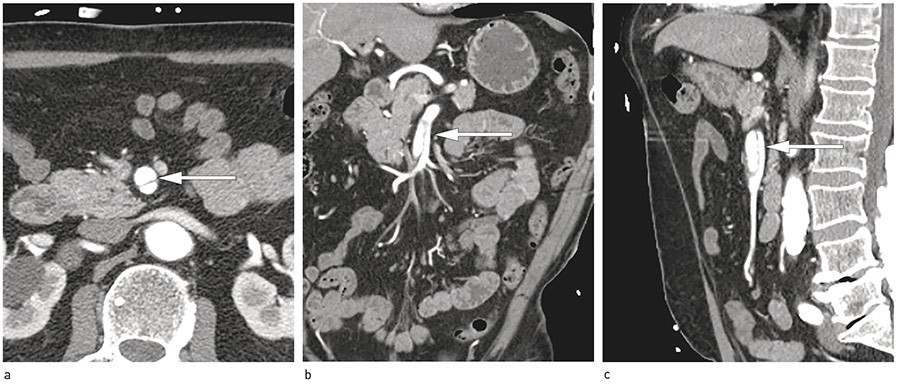

CT thorax med lungeembolismeprotokoll viste ingen tegn til lungeembolisme. CT- angiografi totalaorta viste en 3 cm lang disseksjon i arteria mesenterica superior ut i første høyresidige gren. Det var ingen disseksjon i aorta for øvrig (fig 1).

Disseksjon med stenosering av opptil 60  % av den sanne lumen kan tolereres uten at det forårsaker akutt tarmiskemi, på grunn av kollateral sirkulasjon fra truncus coeliacus og a. mesenterica inferior (9, 13, 14). En stenose av a. mesenterica superior på 50 – 70  % (målt med dupleksultralyd) kan ofte gi symptomer når det i tillegg foreligger okklusjon av truncus coeliacus eller a. mesenterica inferior (9, 13). Vår pasient hadde disseksjon til første høyresidige gren, uten affeksjon av andre grener. Den sanne lumen var åpen og uten stenosering, og det var ingen trombosering av den falske lumen.

A. mesenterica superior-disseksjon avdekkes ofte som et tilfeldig funn på CT abdomen (12). Den ses bedre på CT-angiografi enn på kateterangiografi (4, 5), da sistnevnte ikke vil vise en eventuell totalt trombosert falsk lumen (5). På CT-angiografi kan man se økt diameter, intimalesjon, trombose av falsk lumen, intramuralt hematom eller økt fettinfiltrasjon i segmenter rundt arterien (5, 8). Kateterangiografi vil allikevel være bedre enn CT-angiografi for demonstrering av dobbelt lumen og kollateral blodgjennomstrømming og vil derfor ha størst betydning når pasientens tilstand forverres og det må avgjøres om han trenger kirurgisk eller endovaskulær behandling (5, 16).